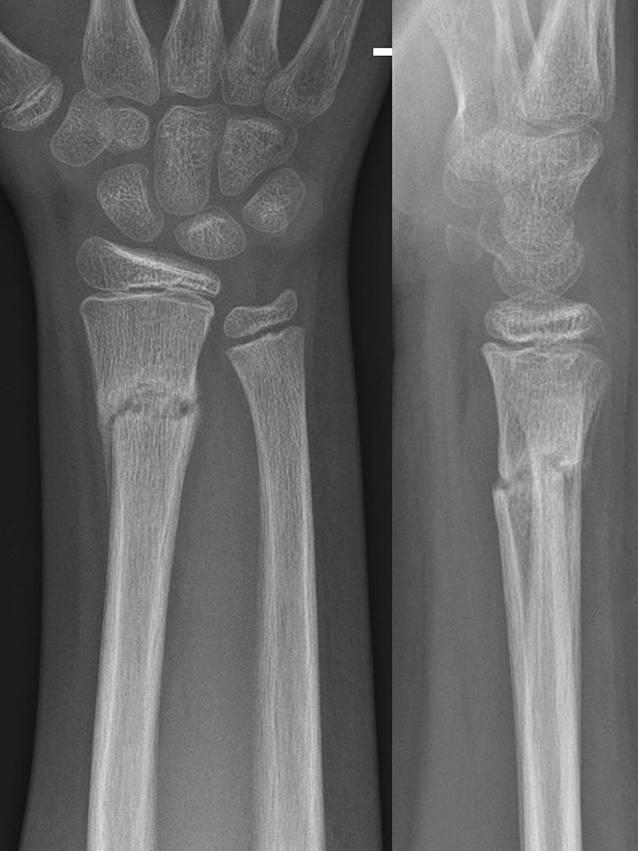

Abb. 10

11-jähriger Junge, Sturz mit Skateboard. Distale metaphysäre vollständige Radiusfraktur mit Achsenknick nach dorsal von rund 30°. Am Unfalltag unter Analgetikagabe zur primären Schmerzbehandlung Anlage eines Oberarmspaltgipsverbandes in Vertikalextension mit gefühlvollem Anmodellieren entgegen der Fehlstellung